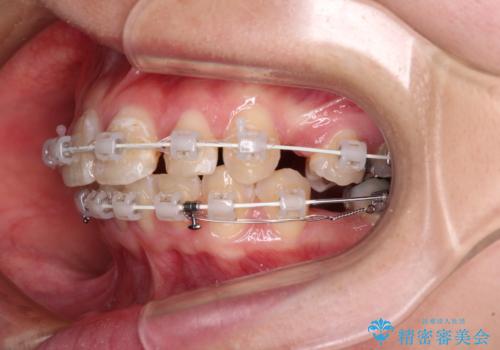

- 審美装置

- 2年7ヶ月

- 10-30回

下顎は過剰歯が埋伏しており、それが原因となってスペースが閉じなかったため、途中で抜歯して速やかに仕上げました。